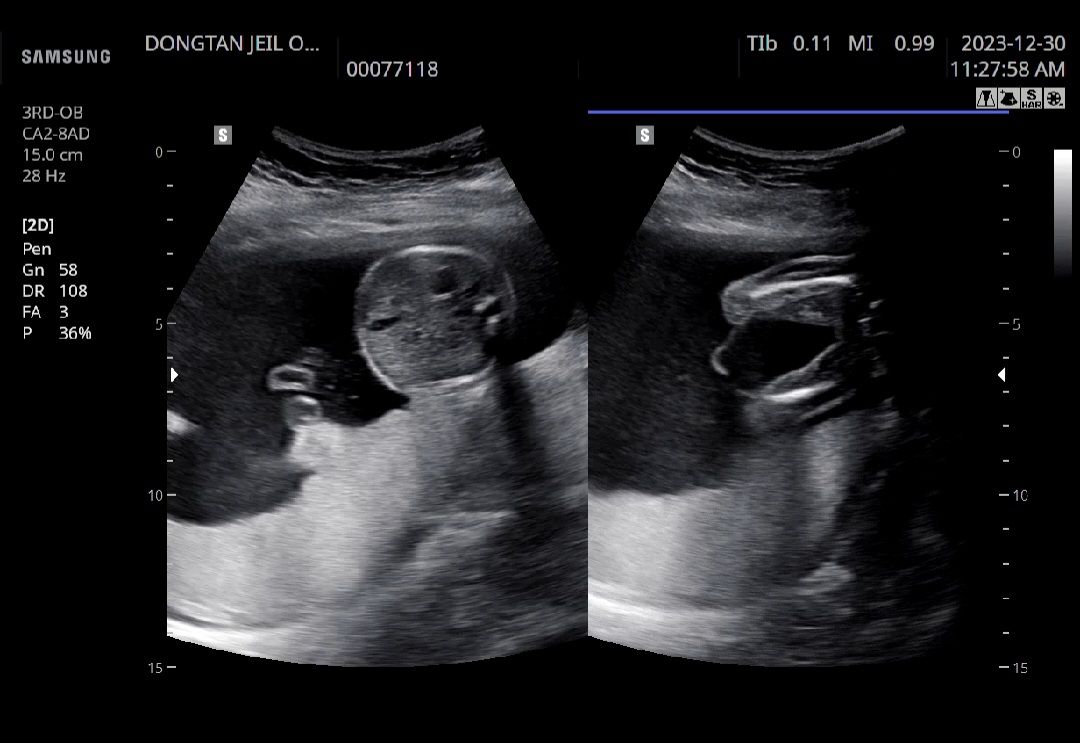

아들?딸?

마스크때문에의사말씀잘못들었어요ㅠㅠ 21주입니다ㅠㅠ 아들?딸? 뭘까요? 첫째아들11살되었어요 둘째아들8살되었어요

딸 같아요~ 우리애기랑 똑같아여 매끈매끈 ㅎㅎ

매끈한거보니 딸이네요 제 촘파사진이랑 똑같아여ㅋㅋㄱㅋㄱㅋ